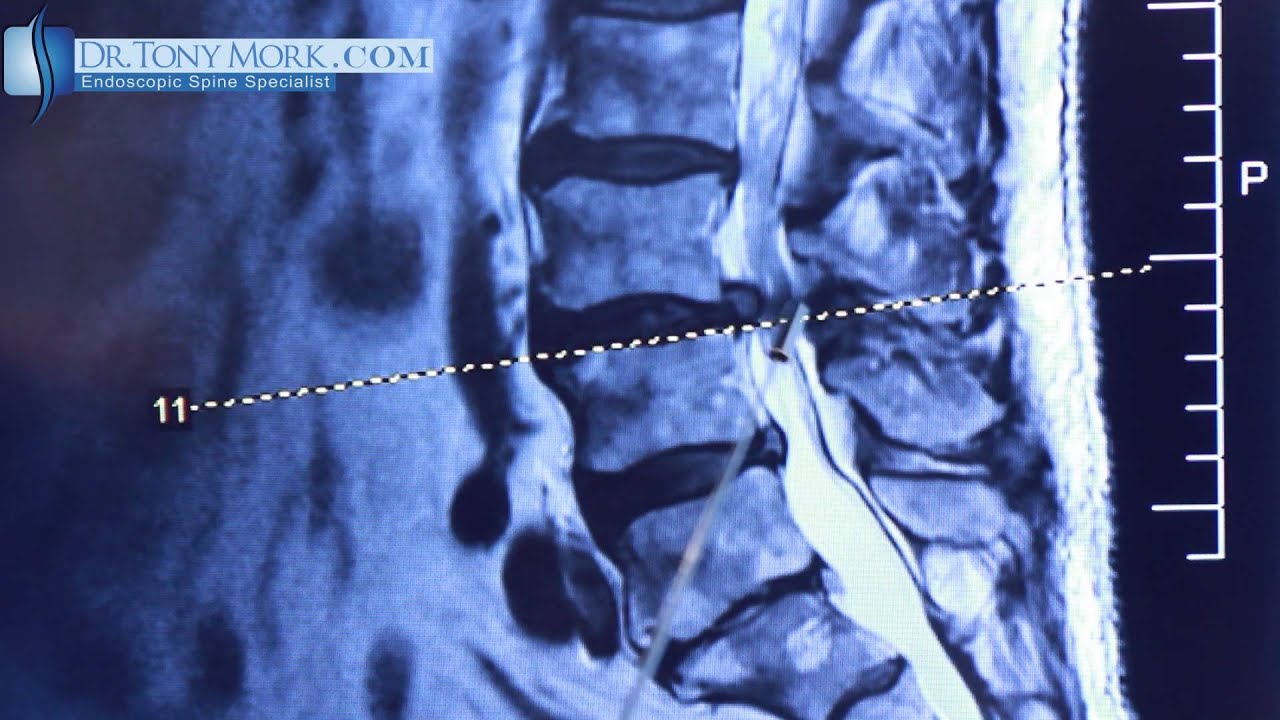

Discectomy vs Laminotomy by Dr. Tony Mork

Discetomy vs. Laminotomy

What do you do about leg (radicular) pain if a transforaminal discectomy doesn't work because of lateral recess stenosis? In this video Dr. Tony Mork describes treating persistent leg pain after a transforaminal discectomy.